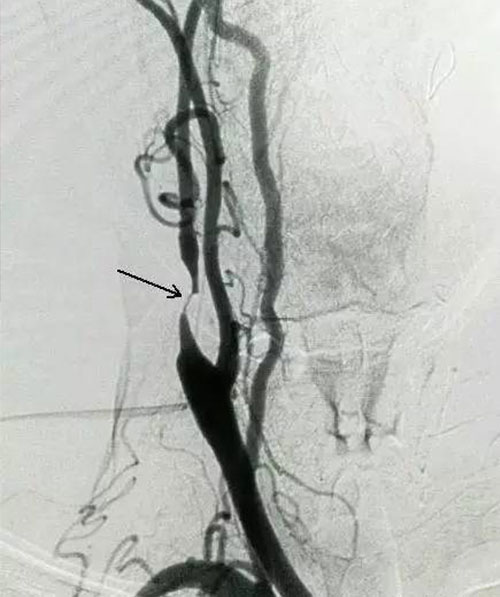

1927年,影像科醫(yī)生通過血管造影發(fā)現(xiàn):一些腦血管正常的人,頸內(nèi)動(dòng)脈卻形成斑塊,造成狹窄,這證明頸內(nèi)動(dòng)脈先于腦血管形成狹窄,頸內(nèi)動(dòng)脈狹窄與腦中風(fēng)是因果關(guān)系,頸內(nèi)動(dòng)脈狹窄是因,腦血管狹窄是果,頸內(nèi)動(dòng)脈狹窄最終會(huì)引發(fā)腦中風(fēng)。

1954年,一名醫(yī)生為一個(gè)腦中風(fēng)病人檢查,發(fā)現(xiàn)病人脖子一側(cè)的頸內(nèi)動(dòng)脈形成了斑塊堵塞,于是就為病人實(shí)施了頸內(nèi)動(dòng)脈斑塊剝離手術(shù),結(jié)果病人的癥狀得到了顯著緩解。這一案例被廣泛報(bào)道,引起了全世界關(guān)注。但是由于手術(shù)的技術(shù)難度大,風(fēng)險(xiǎn)也大,所以并未得到推廣。